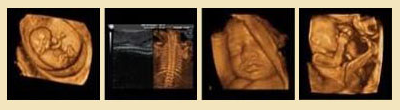

四維彩超宮內(nèi)圖

原理:四維彩超采用三維超聲圖像加上時(shí)間維度參數(shù),能夠?qū)崟r(shí)獲取三維圖像,超越了傳統(tǒng)超聲的限制,能夠顯示您腹中寶寶的實(shí)時(shí)動(dòng)態(tài)活動(dòng)圖像。

優(yōu)點(diǎn):動(dòng)態(tài)立體成像更直觀更清晰:高清成像,可為腹中寶寶拍攝"寫真"和動(dòng)態(tài)錄像。

觀察范圍更廣:能夠多方位、多角度觀察宮內(nèi)胎兒生長(zhǎng)發(fā)育情況,為早期診斷胎兒先天性體表畸形和先天性心臟疾病提供準(zhǔn)確的科學(xué)依據(jù)。

孕婦做四維彩超的佳時(shí)間是22-28周,在這段時(shí)期檢查,因?yàn)樘狠^小,羊水較多,胎兒活動(dòng)度大,體表也比較豐滿,有利于胎兒四維超聲成像和胎兒畸形篩查,是排畸的好時(shí)期。推選閱讀 莆田盛興醫(yī)院做四維彩超好嗎